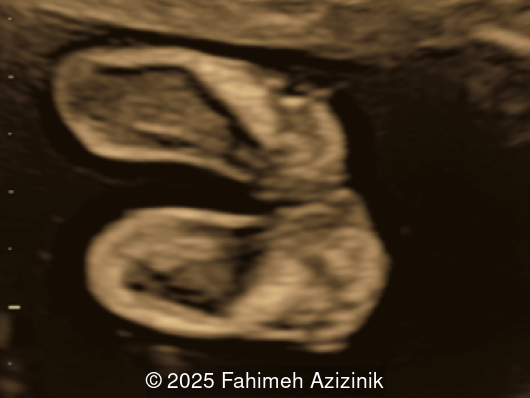

Image 1

• Complex syndactyly of the hands and feet. Complex hand brachysyndactyly with “mitten-like” appearance due to bony fusion of the fingers